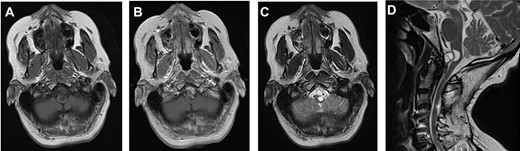

A 64-year-old female status post-two prior spine surgeries presented with recurrent cervical myelopathy. Magnetic resonance imaging (MRI) revealed a 1-cm ventral medullary cyst (Fig. 1A–D), which had enlarged compared with prior imaging. There was significant C1-2 joint arthropathy but no overt instability. She underwent uncomplicated left minimal access far-lateral transcondylar craniotomy for cyst resection. The cyst contained viscous material and was sharply resected, with the exception of the dorsal wall densely adherent to the brainstem. Pathology specimens revealed benign fibroconnective tissue with fibrinous degeneration and focal vascular proliferation (Fig. 2A and B). Immunohistochemical staining for S-100, glial fibrillary acidic protein (GFAP), progesterone receptor (PR), epithelial membrane antigen (EMA) and carcinoembryonic antigen (CEA) was negative; these findings were consistent with a ganglion cyst. Her pain resolved and strength and balance improved post-operatively. Repeat imaging 4 months post-operation demonstrated gross total cyst resection with resolution of the bulbar syrinx and reconstitution of appropriate ventral medullary anatomy (Fig. 3A and B).

MRI findings of a ventral atlantoaxial degenerative cyst with an associated medullary syrinx; axial T1-weighted pre-contrast (A), axial T1-weighted post-contrast (B), axial T2-weighted (C) and sagittal T2-weighted (D) images demonstrate an approximately 1 × 1 cm T1-isointense, T2-hyperintense, rim-enhancing cyst at C1-2 compressing the ventral medulla with an associated a fluid-filled medullary syrinx.